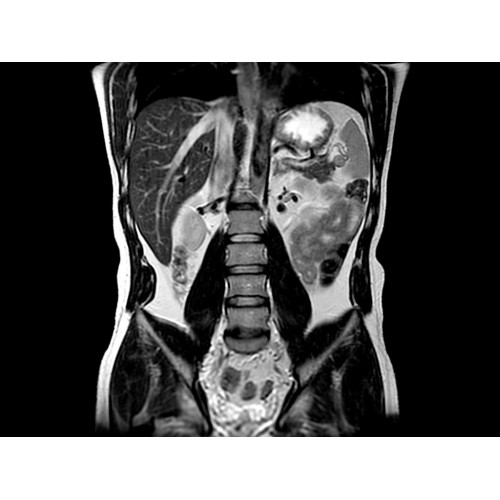

Благодаря принципиально новым технологиям мы расширили возможности МР-томографов с широкими туннелями, совместив непревзойденное качество изображений с высокой производительностью при широком — 50 см — поле зрения.

• Широкое поле зрения — поле зрения шириной 50 см позволяет охватывать крупные анатомические области за меньшее число сканов.

• Визуализация всего позвоночника слиянием двух участков — получить изображение всего позвоночника можно намного быстрее.

• Комплексная оценка печени — первая в отрасли ИП MR-Touch открывает новые возможности диагностики благодаря способности определять различия в жесткости тканей.